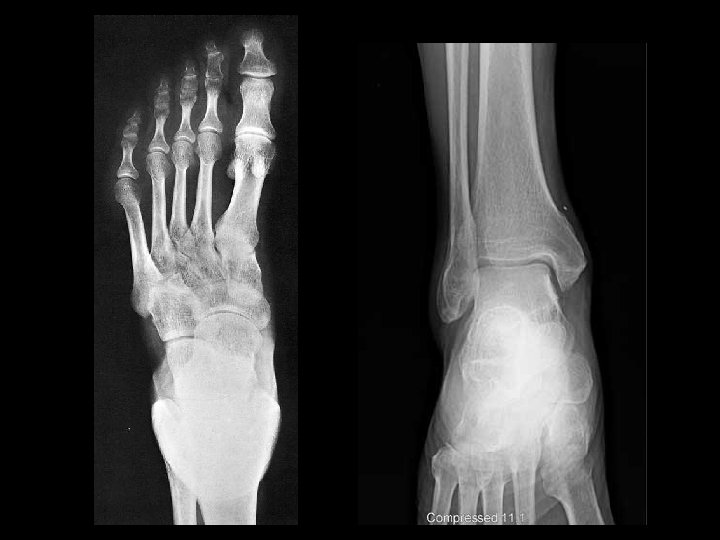

Md - distantia mediodextra 4 - 4, 5 cm Ms - distantia mediosinistra 8 – 9 cm Transverse line of the heart Md + Ms = 15 cm Lg (longitudo) – length of the heart α – inclination of the heart = 45 0 Md Ms α α horizontal line Lg median plane